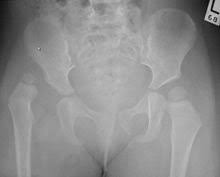

Csípőízületi porckopás (coxarthrosis)

A csípőízületi porcfelszínek elkopása – az ún. artrózis – igen gyakori betegség. Enyhe formájában csak kifejezett terhelés során jelentkezik mérsékelt csípőtáji fájdalom, azonban a súlyos kopás a járást is erősen megnehezíti, vagy akár járásképtelenséget is okozhat, az életminőséget jelentősen rontva.

A csípőízület kopását elősegítő tényezők:

- a túlsúly

- a kifejezett mozgásszervi túlterhelés

- genetikai hajlam

- csípőízület fejlődési zavarai (csípőficam, diszplázia)

- egyes gyermek- és serdülőkori combfej betegségek (combfej elhalás, combfej elcsúszás)

- az autoimmun ízületi gyulladások (pl. a reumatoid artritisz)

- a combfej felnőttkori elhalása, beroppanása

A csípőízületi kopás kezdeti szakaszában jellemző a terhelésre jelentkező csípőtáji fájdalom, valamint a hosszabb pihenés utáni első lépések fájdalmassága, (un. indítási fájdalom) mely néhány lépés után “bejáródik”. Ilyenkor a csípőízületi porcfelszín felpuhulása, később annak felrostozódása figyelhető meg, mely a fokozatosan leváló kisebb rostok miatt az ízület izgalmi állapotát, gyulladását eredményezi; utóbbi felelős a fájdalom kialakulásáért.